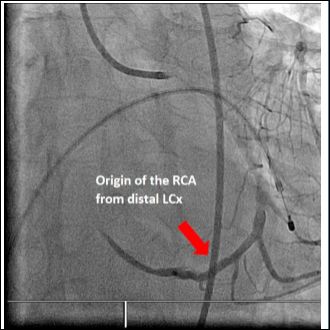

Our second case was a 67-year-old male with no prior cardiac history who presented with an acute anterior STEMI. Emergency coronary angiography revealed a single coronary artery with a critical stenosis in the proximal LAD (culprit lesion) and RCA arising from the distal circumflex artery (Figure 2). Successful primary PCI of proximal LAD was performed (Figures 3 & 4). Echocardiography was done during admission showing no associated structural heart disease. Patient was discharged after 4 days of hospital stay without any complications and remained asymptomatic during follow up.

Figure 2: Anomalous Origin of the Right Coronary Artery (RCA) from the Distal Circumflex Artery (LCx).